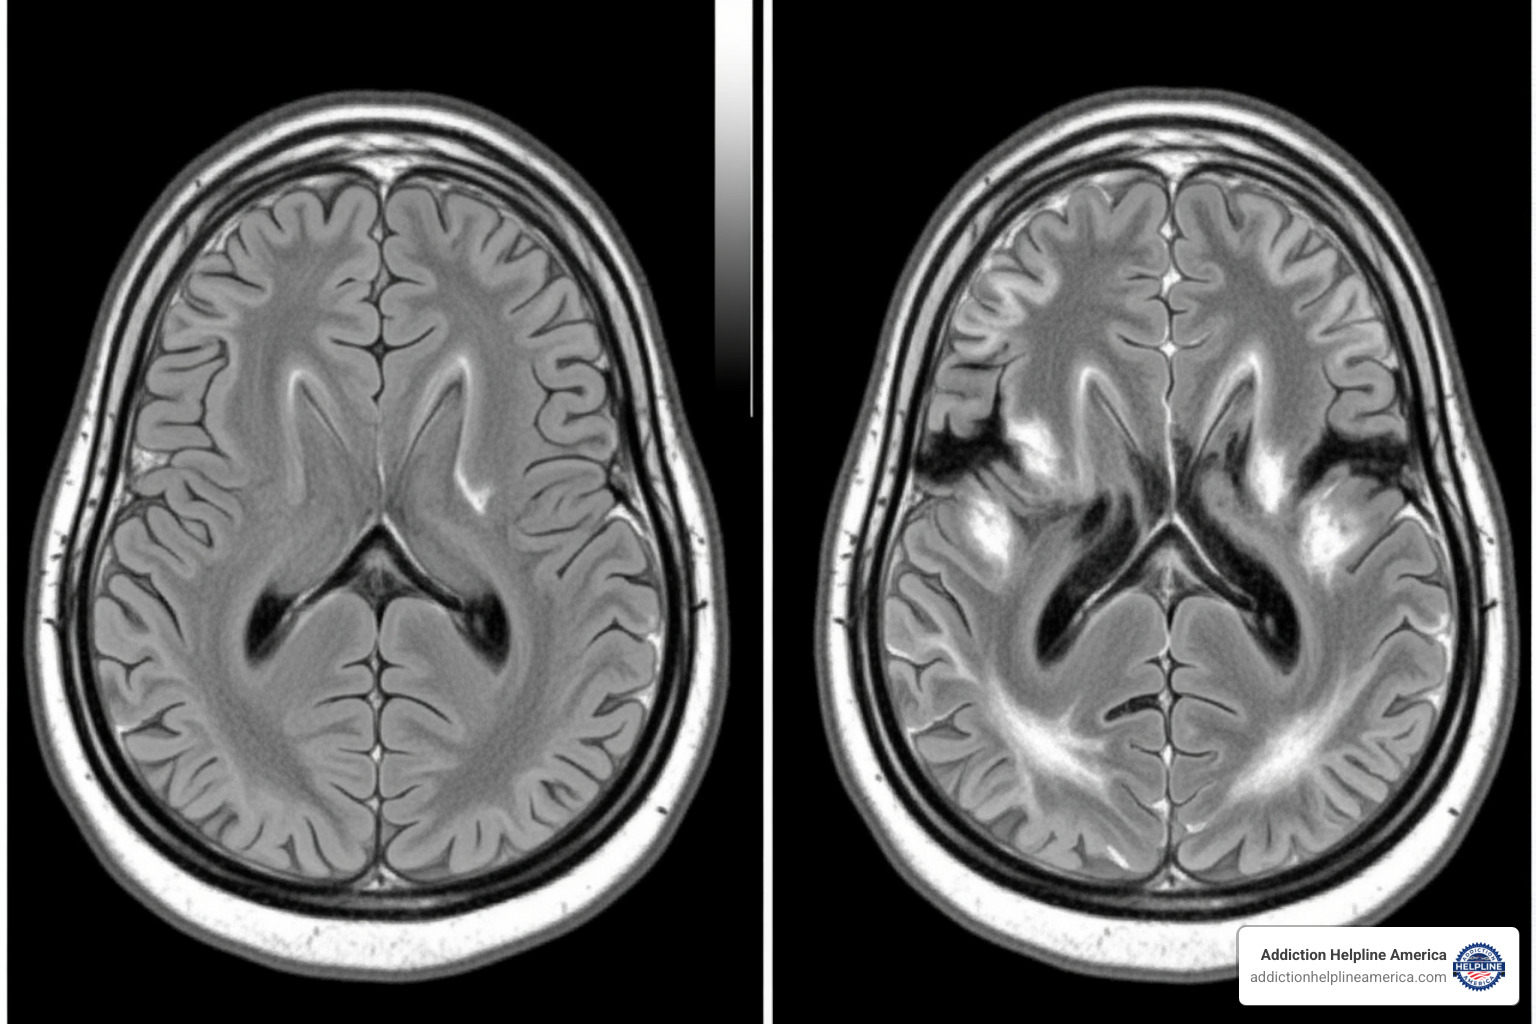

Can Meth Cause Permanent Brain Damage?

Chronic meth use can damage dopamine and serotonin systems, affecting mood, motivation, memory, attention, and decision-making. While some changes may persist, many people improve with sustained abstinence and treatment. The brain can heal over time—another reason to start early. See Meth Addiction Effects.

Yes, chronic exposure can damage dopamine and serotonin systems, leading to lasting cognitive and emotional problems. Still, many people improve with sustained abstinence and treatment—the brain can heal over time. Learn more at Meth Addiction Effects.